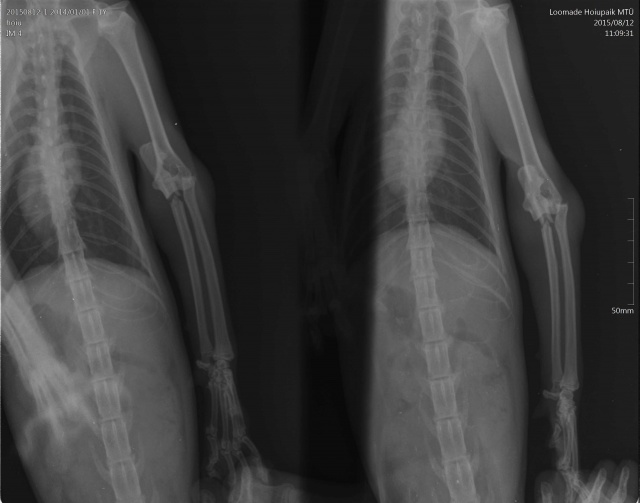

Kass on opereeritud! - Кошка прооперирована.

Диагноз:

- вывих локтевого сустава

- перелом локтевой кости

- межмыщелковый перелом плеча(?)